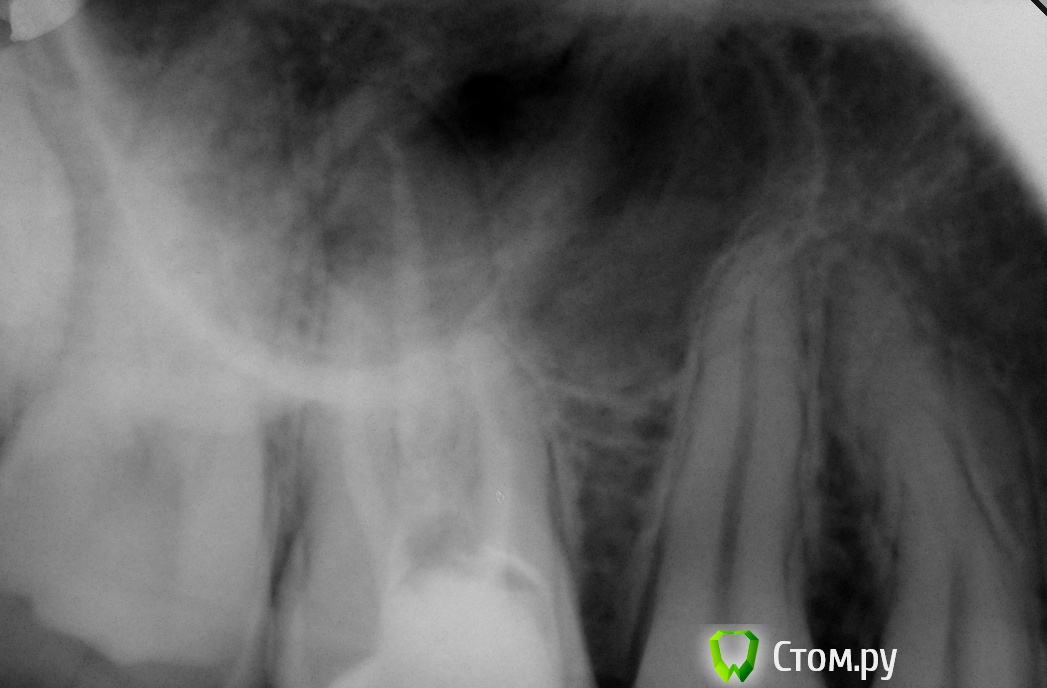

xSlon Опубликовано 13 августа, 2014 Поделиться Опубликовано 13 августа, 2014 Доброго времени суток!Прошу вашей помощи по сложному зубу, который не могут вылечить уже очень длительное время. Около 3х лет назад обнаружил, что при постукивании по 16му зубу(он был запломбирован совсем давно, не помню даже где и в каком году) появляется небольшая боль. Зуб не мешал, не доставлял беспокойств, но решив, что в таких случаях нужно действовать превентивно, пошел к стоматологу и рассказал о проблеме. Он посмотрел зуб(без вскрытия), сказал что никаких признаков боли не видит и считает что нужно удалять нерв. Поскольку зуб проблем не доставлял, я отказался.В течение этих трех лет состояние не ухудшалось, но я еще два раза ходил к разным стоматологам, описывал симптомы, они смотрели зуб, никаких признаков болезни не видели и советовали заниматься зубом когда он будет доставлять настоящие неудобства.В середине октября 2013 года ситуация ухудшилась, зуб начал периодически не сильно болеть, реагировать на холодное и горячее. В середине декабря ситуация сильно ухудшилась, зуб начал сильно болеть, сильно реагировать на холодное и горячее, сильно болеть даже при простом касании. Я обратился в стоматологию1 к врачу1, где мне вскрыли зуб, сказали что обнаружили под пломбой кариес, из-за кариеса произошло воспаление нервов и нужно удалять нервы в зубе. Боль была очень значительной, я не раздумывая согласился. Мне вскрыли зуб, поставили обезболивающее(или лекарство - точно не знаю), и сказали прийти через 7 дней, боль прошла. Через 7 дней мне обработали каналы и запломбировали Metapex'ом, сказали прийти в феврале(возможно еще удалили лекарство, точно не помню). В феврале мне за 1 посещение запломбировали постоянно каналы и за 2е посещение запломбировали зуб. К середине февраля лечение закончилось, жалоб не было. Единственное - удивляло что зуб, несмотря на удаление нервов, по старому реагирует на постукивание небольшой болью, но я не придал этому большого значения.Спустя 2 месяца, в середине апреля, остро заболел тот же самый зуб, с теми же симптомами - сильная боль, сильная реакция на холодное и горячее, сильная боль при касании. Врач1 был в отпуске, поэтому я пошел к Врачу2 в ту же самую Стоматологию1. Описал ситуацию, Врач2 посмотрела мою карточку, вскрыла зуб, осмотрела его, сказала что где-то должен быть 4й канал, но она не может его найти, сказала что вставила куда-то в зуб лекарство, сказала прийти через неделю.Боль утихла, пришел через неделю к тому же Врачу2, повторно вскрыли зуб, повторно поставили лекарство, но Врач2 сказала что 4го канала, который там должен быть, она не видит. Посоветовала обратиться к другому врачу, возможно, в другую стоматологию Через неделю, уже в начале мая, пришел повторно, запломбировали каналы Metapex'ом, поставили временную пломбу. По совету знакомых, в начале июня обратился к частному Врачу3, который специализируется на работе под микроскопом. Описал ей ситуацию, она вскрыла зуб, нашла четвертый канал, вставила туда лекарство, сказала прийти через неделю. Через неделю реакция зуба на слабые постукивания сохранилась, на приеме у Врача3 поставили более сильное лекарство(насколько я помню, с антибиотиком), прописала дополнительно в течении 5 дней пропить сильные антибиотики, сказала прийти через 10 дней. Через 10 дней, в конце июня, та же реакция зуба сохранилась. На приеме у Врача3 решили окончить лечение, потому как Врач3 на следующий день уходила в отпуск, а я, через несколько дней, уезжал в командировку. Перед отъездом пошел в Стоматологию1 к Врачу2, чтобы снять лекарство и временно запломбировать каналы и поставить временную пломбу. Врач2 сказала, что при вскрытии зуба она увидела 4й канал, попыталась определить длину канала с помощью прибора, используя самый тонкий инструмент(как я понял - это некая игла, подсоединенная к прибору, ее всовывают в канал, чем ближе кончик иглы к концу канала, тем сильнее он пищит), определить длину канала ей не удалось. Она предположила, что либо канал очень узкий, либо он изгибается, поэтому не удается дойти до конца канала.В командировке, в середине июля обновлял временную пломбу(от нее отвалился небольшой кусочек) в Стоматологии2, вкратце описал проблему Врачу4, он посоветовал использовать(дословно с листочка, который он мне дал) пломбировку материалом для к/к Forfenan Forident(резорцин-формалиновая паста). Сказал, что при таком методе, воспаленный нерв полностью обволакивается пастой, которая гермитизирует нерв, не давая разиваться воспалительному процессу. Сам воспаленный нерв остается, но организм, со временем, справляется с ним сам.Вернувшись из командировки, я пошел, по советам родственников, в Стоматологию3, к Врачу5. Описал ситуацию, сделал панорамный и прицельный снимки. Врач5, не вскрывая зуб, сказала что считает, что необходимо применить метод депофореза. Прошу вас, пожалуйста, посоветовать, каким образом вылечить этот зуб? Стоит ли попробовать резорцин-формалиновую пасту? Стоит ли делать метод депофореза? Возможно есть какие-то другие методы лечения? Прикладываю все снимки зуба из Стоматологии1Панорамный снимок из Стоматологии3, сделан 12 августа. https://yadi.sk/i/_hIqGP1IZaT4Y Ссылка на комментарий

Бобр Опубликовано 28 августа, 2014 Поделиться Опубликовано 28 августа, 2014 Интересно, возможно сначала идет один МБ, а потом он где нибудь в средней трети раздваивается? Возможно трещина. Возможно парадонтальный карман на медиальной поверхности. Честно говоря интересная история. Ссылка на комментарий

faity Опубликовано 28 августа, 2014 Поделиться Опубликовано 28 августа, 2014 а у вас КТ есть? Ссылка на комментарий

xSlon Опубликовано 31 августа, 2014 Автор Поделиться Опубликовано 31 августа, 2014 Интересно, возможно сначала идет один МБ, а потом он где нибудь в средней трети раздваивается? Возможно трещина. Возможно парадонтальный карман на медиальной поверхности. Честно говоря интересная история.Каким образом можно определить раздвоение/трещину/парадонтальный карман? Я бы сообщил эту информацию врачу, попросил бы посмотреть.а у вас КТ есть?Нет. Поможет ли при выявлении проблемы с зубом? Записался на 3 сентября к Врачу3, попрошу поставить лекарство, потом постоянно запломбировать. Делаю все это, потому что 9го числа скорее всего придется уезжать в очень длительную поездку, заниматься зубом не смогу Ссылка на комментарий

faity Опубликовано 31 августа, 2014 Поделиться Опубликовано 31 августа, 2014 кт поможет диагностирвать Ссылка на комментарий